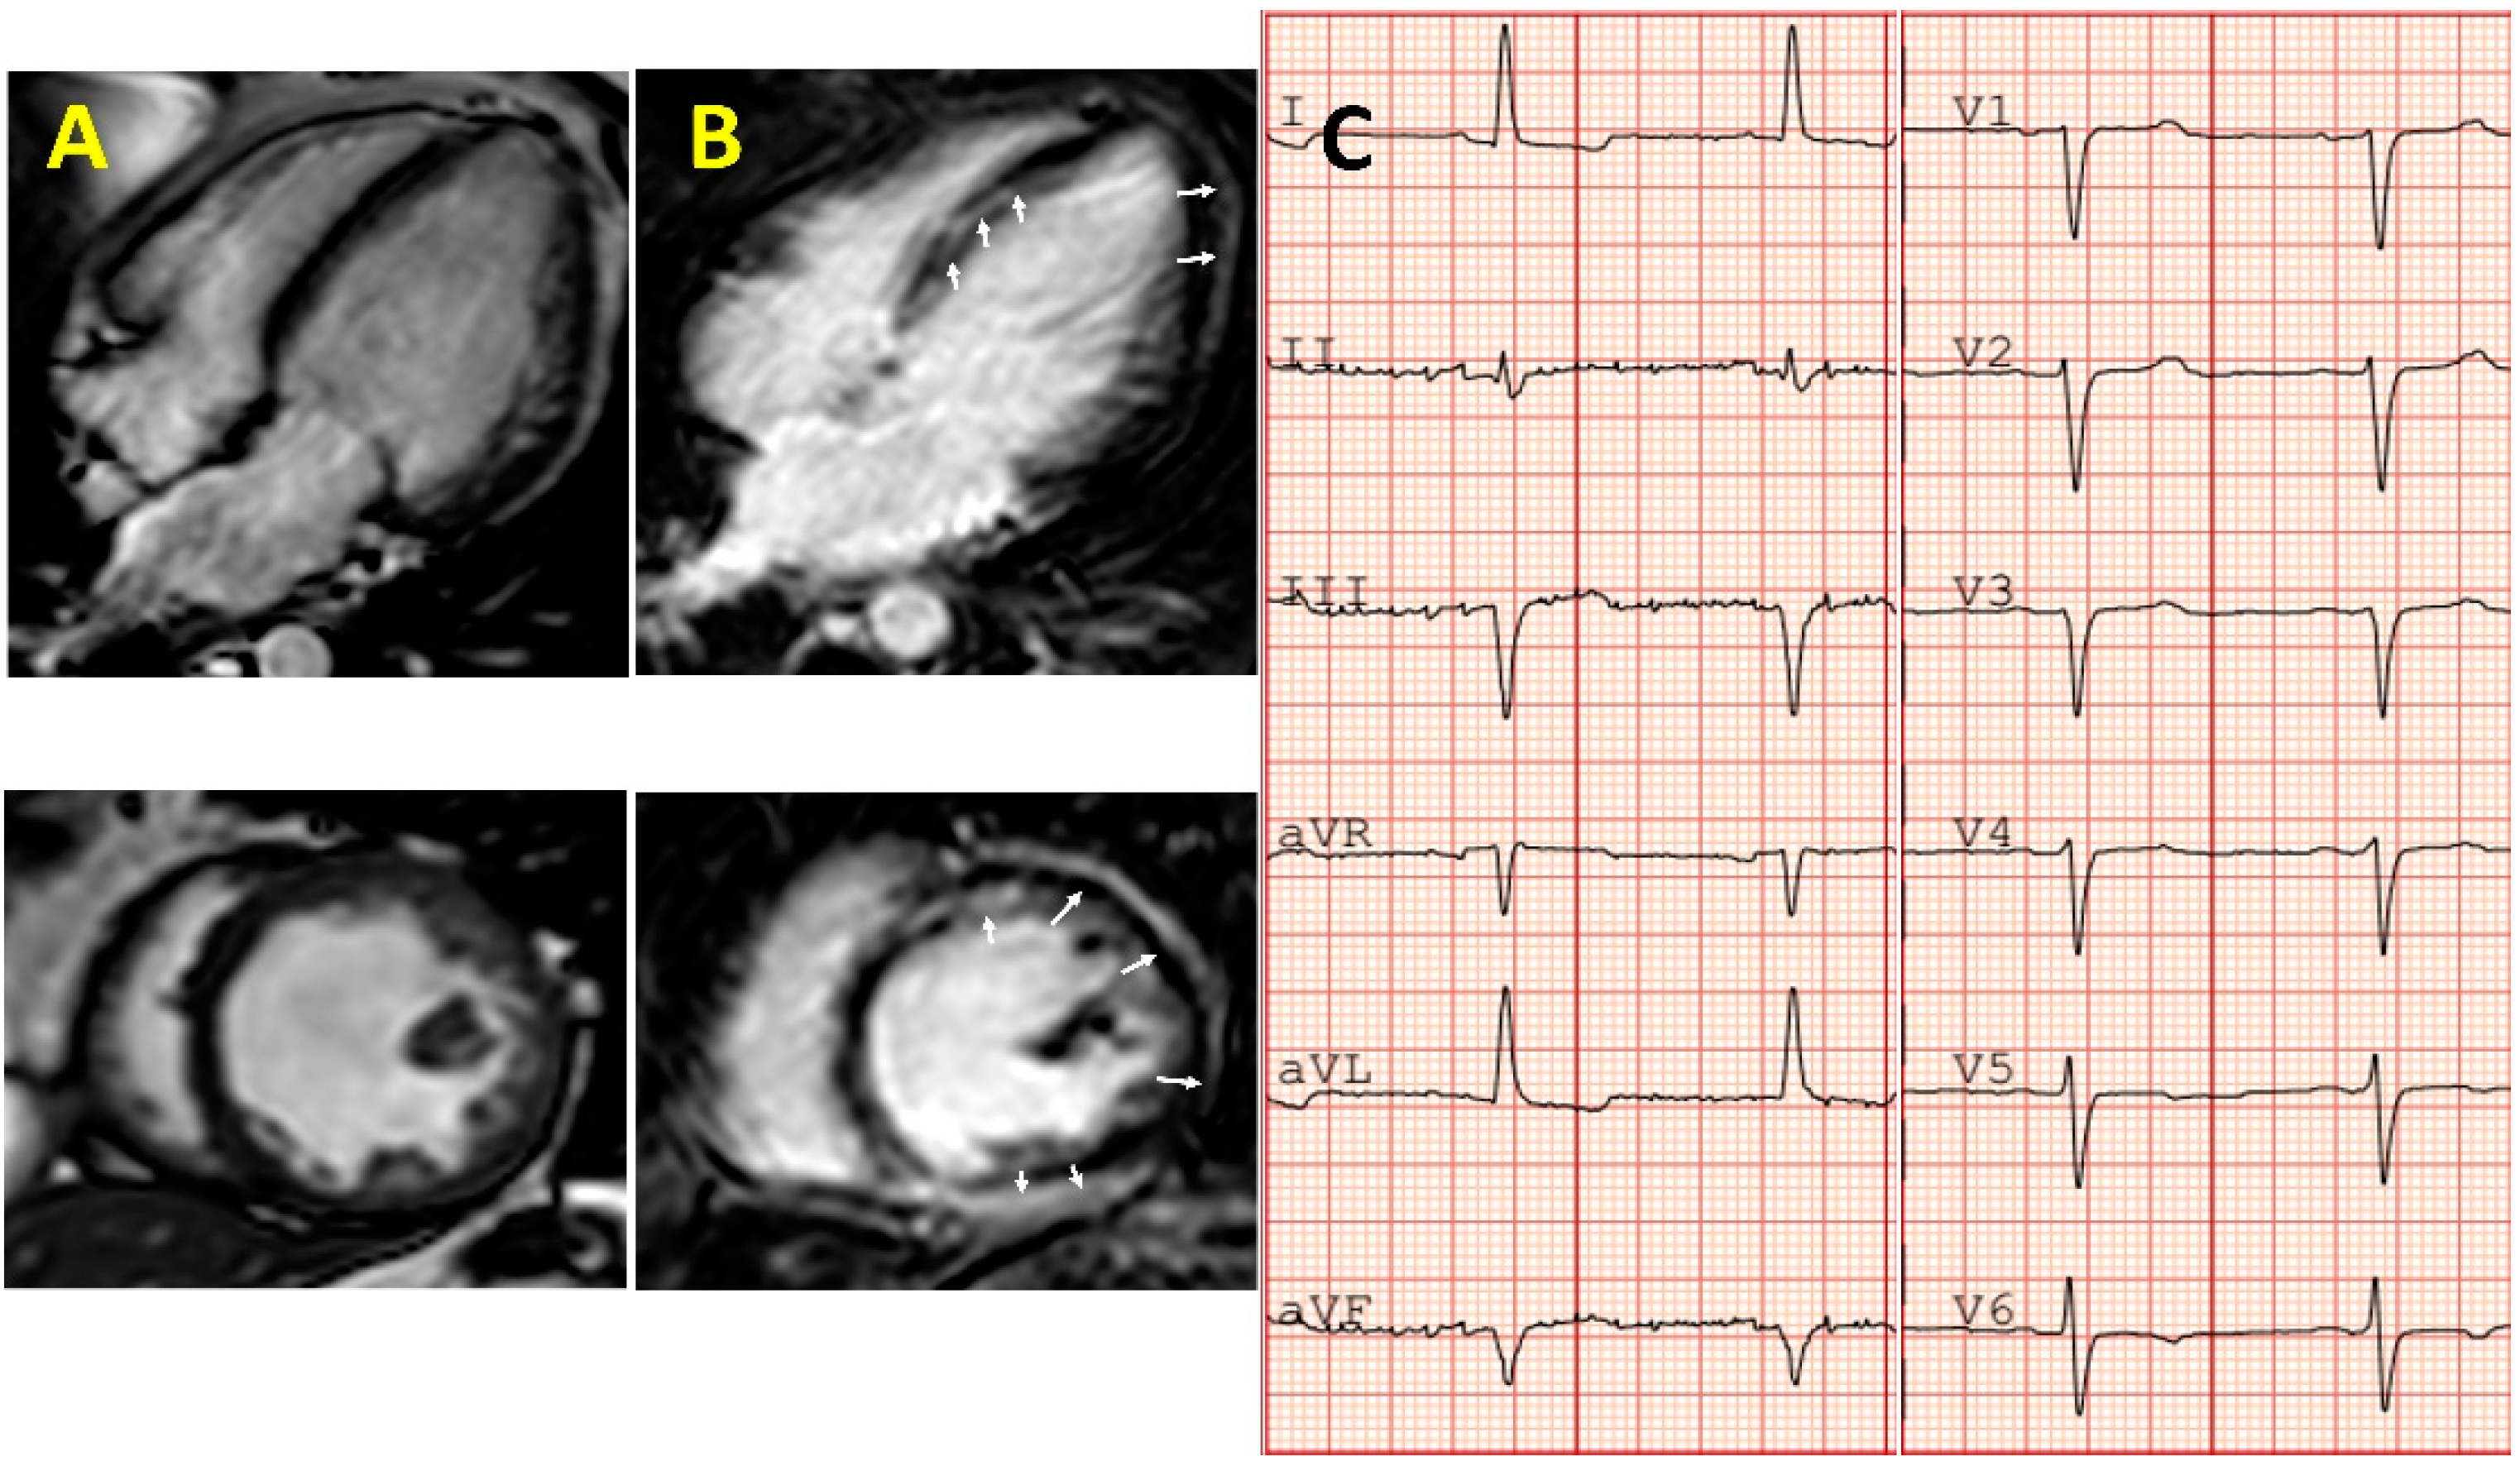

3. Evaluation of Cardiac Injury from Chemotherapy

6. Importance of Genetic and Family Study in Patients with Severe Cardiotoxicity

- Holmström, M.; Kivistö, S.; Heliö, T.; Jurkko, R.; Kaartinen, M.; Antila, M.; Reissell, E.; Kuusisto, J.; Kärkkäinen, S.; Peuhkurinen, K.; et al. Late gadolinium enhanced cardiovascular magnetic resonance of lamin A/C gene mutation related dilated cardiomyopathy. J. Cardiovasc. Magn. Reson. 2011, 13, 30. [Google Scholar] [CrossRef] [PubMed] [Green Version]

- Becker, M.A.; Cornel, J.H.; Van De Ven, P.M.; Van Rossum, A.C.; Allaart, C.P.; Germans, T. The prognostic value of late gadolinium-enhanced cardiac magnetic resonance imaging in nonischemic dilated cardiomyopathy: A Review and Meta-Analysis. JACC Cardiovasc. Imaging 2018, 11, 1274–1284. [Google Scholar] [CrossRef]

- Fallah-Rad, N.; Walker, J.; Wassef, A.; Lytwyn, M.; Bohonis, S.; Fang, T.; Tian, G.; Kirkpatrick, I.D.; Singal, P.K.; Krahn, M.; et al. The utility of cardiac biomarkers, tissue velocity and strain imaging, and cardiac magnetic resonance imaging in predicting early left ventricular dysfunction in patients with human epidermal growth factor receptor II–positive breast cancer treated with adjuvant trastuzumab therapy. J. Am. Coll. Cardiol. 2011, 57, 2263–2270. [Google Scholar] [CrossRef]

- Galán-Arriola, C.; Lobo, M.; Vílchez-Tschischke, J.P.; López, G.J.; De Molina-Iracheta, A.; Perez-Martinez, C.; Aguero, J.; Fernández-Jiménez, R.; Martín-García, A.; Oliver, E.; et al. Serial magnetic resonance imaging to identify early stages of anthracycline-induced cardiotoxicity. J. Am. Coll. Cardiol. 2019, 73, 779–791. [Google Scholar] [CrossRef]